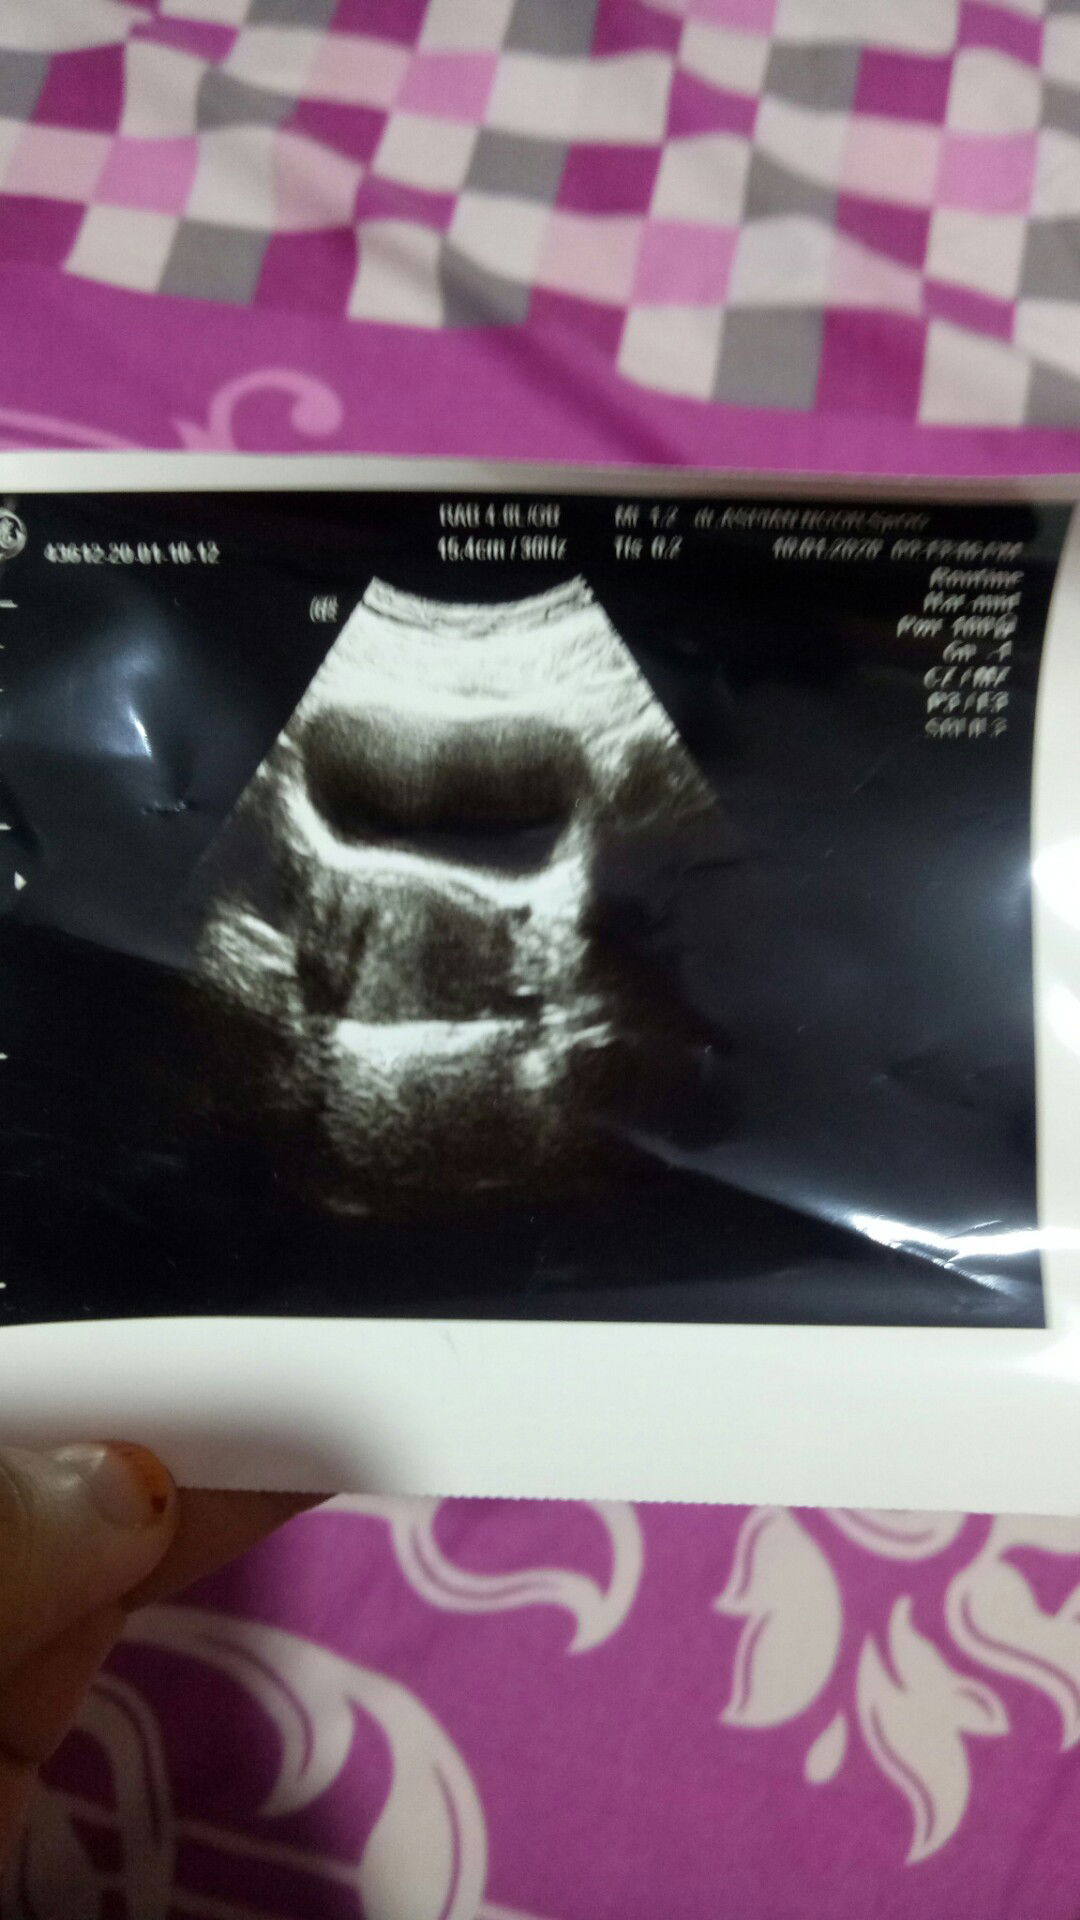

HPL AKHIR SEPTEMBER

Bunda yg hpl nya akhir september udah ngerasain apa aja nih ?

Hpl antara hari ini atau besok tp masih kenceng2 biasa blm datang mulesnya bund,